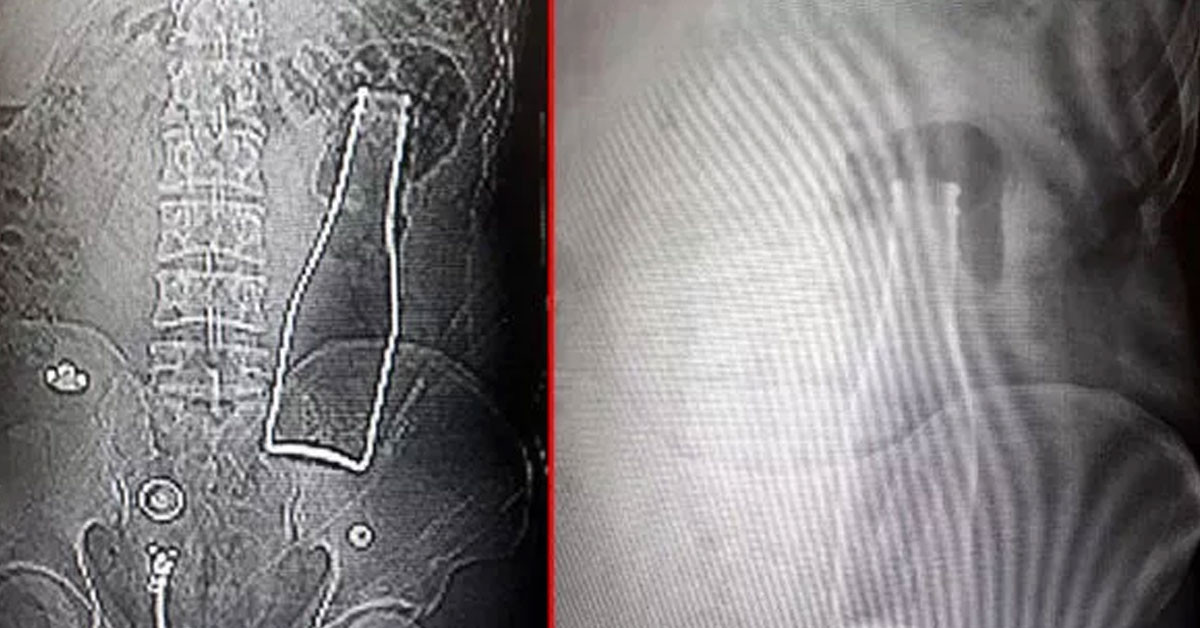

ABD'de bir kadın odası partneri ile eğlenceyi ararken yaptıkları yanlış bir hareket yüzünden hemen taşıdılar. Bu da her türlü seks oyunlarının sonu hastanelik olan insanlara akıllara geitrdi.

Sevgilisi ile yaramazlık yapmak isteyen kadın ve erkek arkadşası yapmak daha eğlenceli bir yatak hayatları olsun diye asla yapmamaları gereken bir şey yaptı. Saatler ilerledikçe büyük bir acı hisseden kadın en sonunda dayanamadı ve utana sıkıla koştu. Bu da akıllara seks kazalarını dile getirdi.